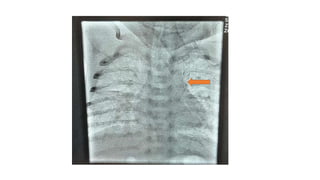

• Repeat Echocardiography showed: Supracardiac TAPVR with vertical

vein obstruction. Moderate size ASD secundum.Dilated right atrium

and ventricle. Severe tricuspid regurgitation 97 mmHg. LVEF 67%.

Hospital course • RepeatEchocardiography showed: Supracardiac TAPVR with vertical vein obstruction. Moderate size ASD secundum.Dilated right atrium and ventricle. Severe tricuspid regurgitation 97 mmHg. LVEF 67%. • Other laboratory investigation were in normal limits. • Baby admitted in NICU for vertical vein stenting.